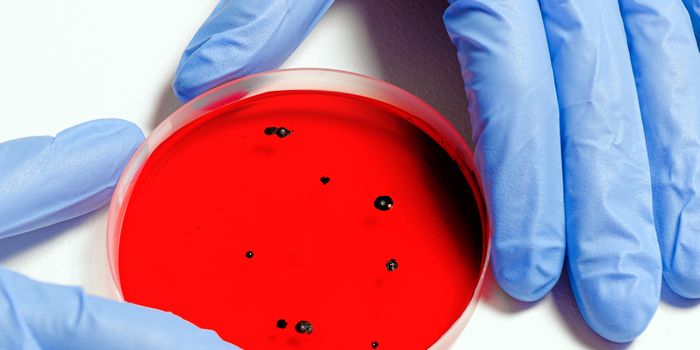

MAR 30, 2022Clinical & Molecular DXStrategies to Improve Your Lab’s Blood Culture Process A blood culture is a routine laboratory test in which blood ...